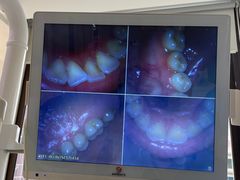

• 好大夫口腔(广州店)

• -好大夫口腔(广州店)

Jerry杰瑞 | 24-01-11